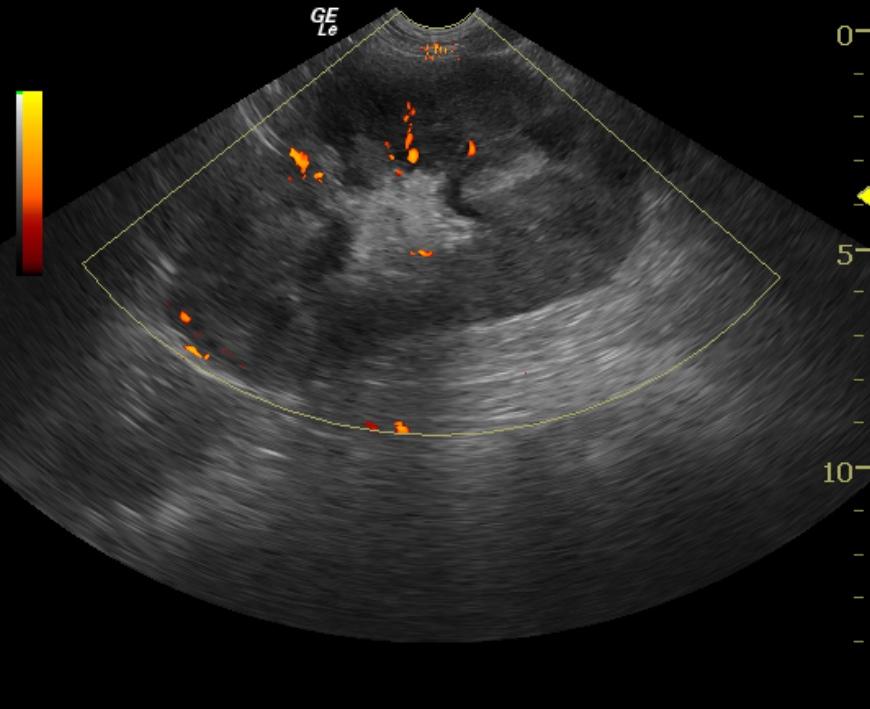

The kidneys revealed severe renomegaly (8 cm each) with multiple target type hypoechoic lesions. Round cell neoplasia is suspected. No evidence of acute or chronic inflammatory or infarctual changes were noted.

Ultrasound-guided fine needle aspirates of the left kidney were performed. Cytology revealed malignant lymphoma. The cell morphology suggested intermediate to high grade B-cell lymphoma.

Likely bilateral renal neoplasia such as lymphoma or other round cell disease.